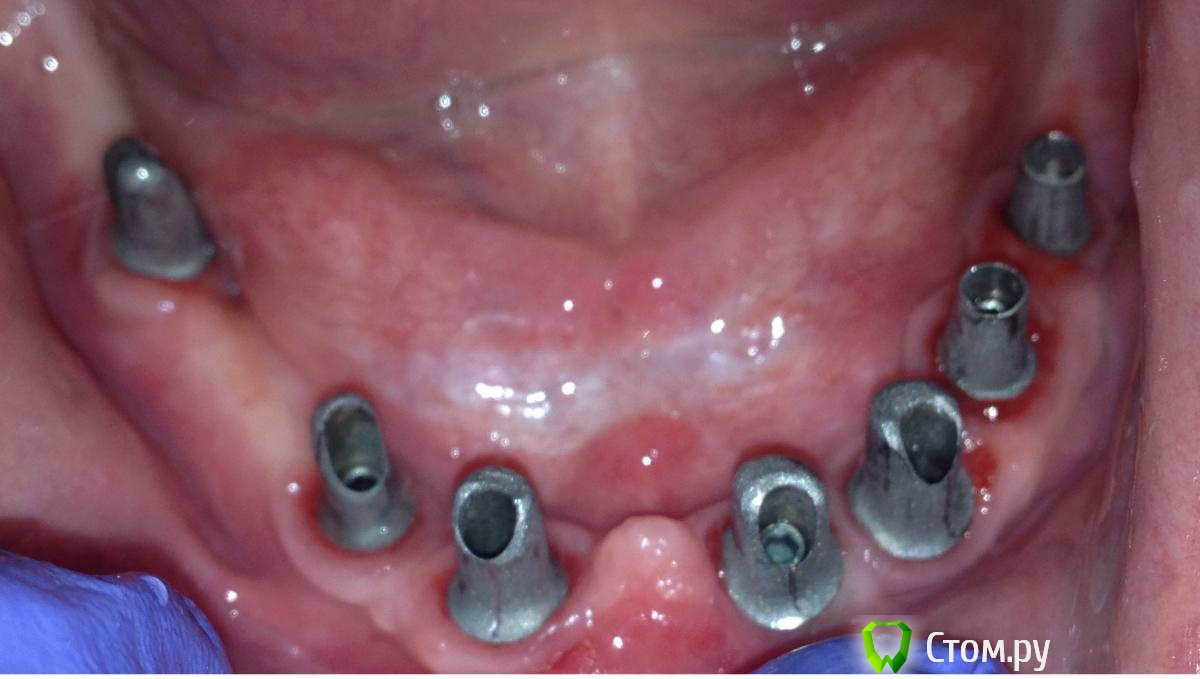

MaxDok Опубликовано 10 апреля, 2014 Автор Поделиться Опубликовано 10 апреля, 2014 Еще похожая работа 5 1 Ссылка на комментарий

MaxDok Опубликовано 11 апреля, 2014 Автор Поделиться Опубликовано 11 апреля, 2014 (изменено) Работа понравилась.Какая была временная конструкция? Слепок под постоянную конструкцию снимался с уровня абатмента? СпасибВременнная конструкция на временных титановых абатментах , обычная пластмассовая облицовка ,винтовая фиксация.Отттиск с уровня имплантов снимал , фото индивидуальной ложки и самого оттиска не могу найти. Изменено 11 апреля, 2014 пользователем MaxDok 6 Ссылка на комментарий

MaxDok Опубликовано 8 мая, 2014 Автор Поделиться Опубликовано 8 мая, 2014 Спасибо . Я только ортопедию делал ну и присутствовал на установке , из навигации были изготовлены два псп , по ним и ориентировались . Ссылка на комментарий

Evikrol Опубликовано 14 мая, 2014 Поделиться Опубликовано 14 мая, 2014 Как эта пластмасса называется, красная которая на трансферах? И склеивали во рту чем? Ссылка на комментарий

MaxDok Опубликовано 14 мая, 2014 Автор Поделиться Опубликовано 14 мая, 2014 Как эта пластмасса называется, красная которая на трансферах? И склеивали во рту чем?Pattern Resin , соединял во рту им же . Ссылка на комментарий